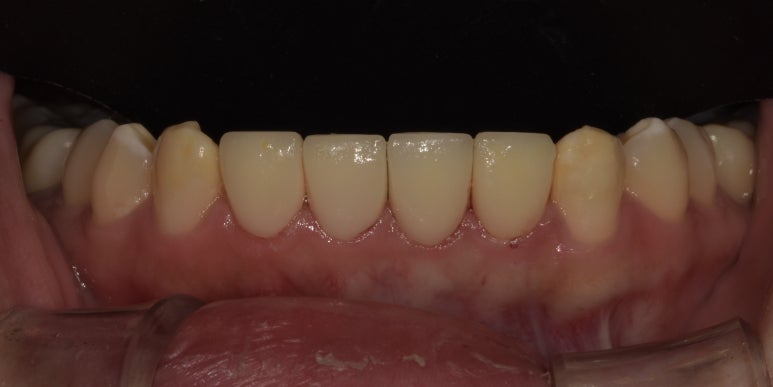

20231107 아랫니 라미네이트 전

20231120 아랫니 라미네이트 후